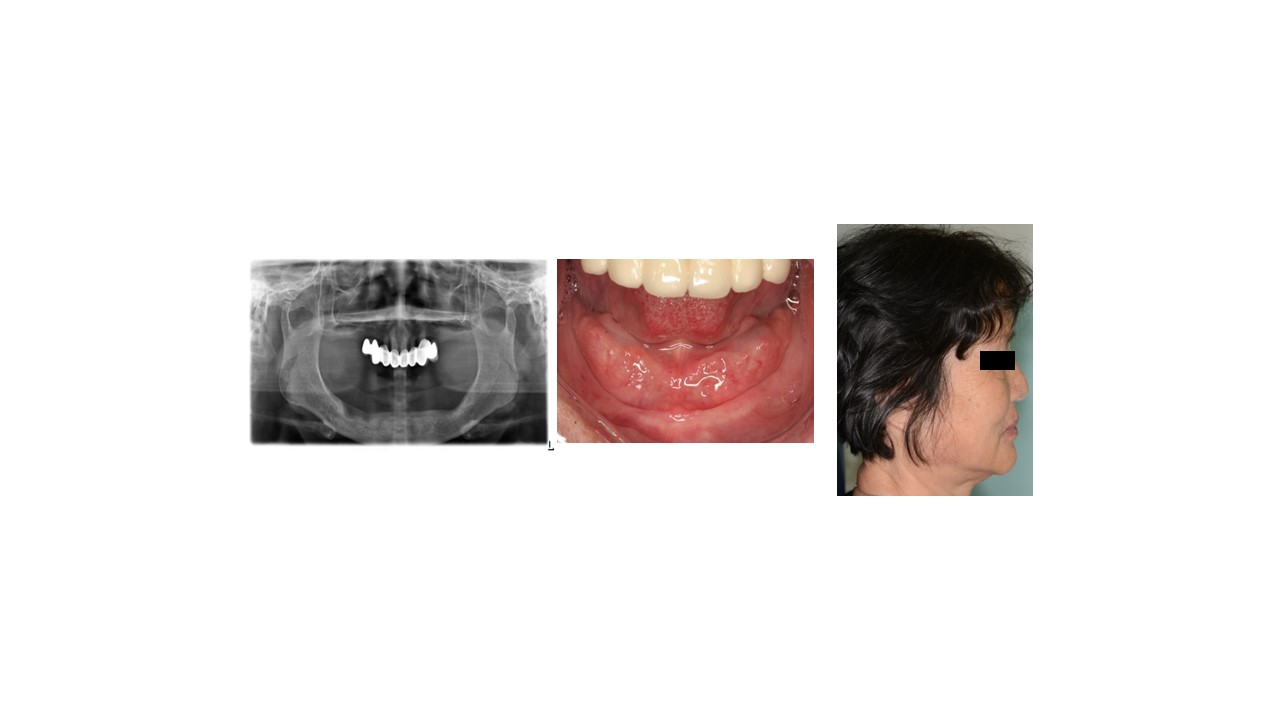

种植科普